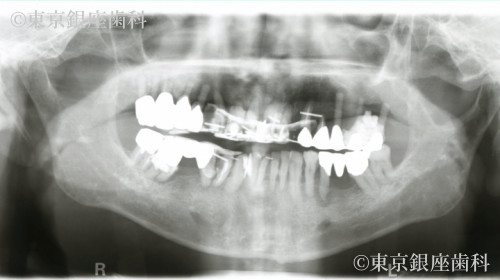

がん治療の既往があり複雑な治療歴を経てワンデイインプラントで噛む機能を回復した70歳代男性の症例

長年の治療で口腔内がつぎはぎ状態で違和感を抱えていたが、ワンデイインプラントで即日改善。1箇所結合不全があったが再手術で問題なく回復した。

ワンデイインプラント(上下)